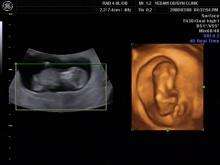

3D ultrasound

3D ultrasound is a medical ultrasound technique, often used in obstetric ultrasonography (during pregnancy), providing three-dimensional images of the fetus. Three-dimensional ultrasound, also known as phased array ultrasonics, is used extensively in the non-destructive evaluation of materials for purity and failure assessment.

There are several different scanning modes in medical and obstetric ultrasound. The standard common obstetric diagnostic mode is 2D scanning.[1] In 3D fetal scanning, however, instead of the sound waves being sent straight down and reflected back, they are sent at different angles. The returning echoes are processed by a sophisticated computer program resulting in a reconstructed three-dimensional volume image of the fetus's surface or internal organs, in much the same way as a CT scan machine constructs a CT scan image from multiple x-rays.

Clinical use of this technology is an area of intense research activity especially in fetal anomaly scanning[3][4][5] but there are also popular uses that have been shown to improve fetal-maternal bonding.[6] 4D fetal ultrasounds are similar to 3D scans, with the difference associated with time: 4D allows a 3-dimensional picture in real time, rather than delayed, due to the lag associated with the computer constructed image, as in classic 3-dimensional ultrasound.

3D ultrasounds are best done at 24–32 weeks, and ideally between 26 and 30 weeks. Most 3d imaging centers advise customers to come in between 26 and 28 weeks to get the best images.